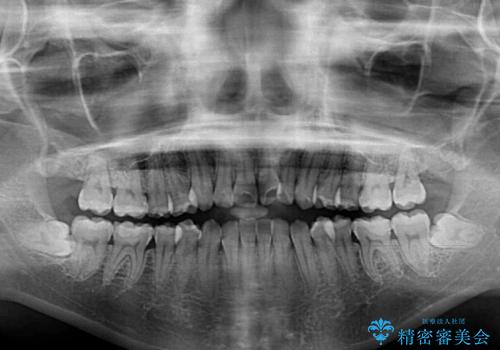

- 前歯の上下スペースによる食べにくさを気にして来院された患者様です。

インビザラインにより上下の前歯の隙間を閉じていくこととしました。

前歯のデコボコの解消と並行して上下の奥歯を圧下させるようにすることで、前歯を接触させるように計画しました。

上下の隙間に舌が入り込むことがオープンバイトの原因であったため、舌の筋肉のトレーニングも並行して行い、後戻りの抑制を図りました。